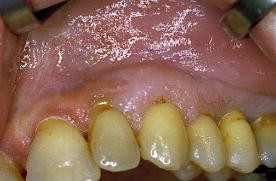

Die proliferative verruköse Leukoplakie (PVL) ist eine seltene Variante der oralen Leukoplakie (OL) mit hoher Transformationstendenz. Sie beginnt als plane Hyperkeratose. Im Verlauf tritt die verruköse Komponente in Erscheinung.

Das klinische Bild der PVL entsprach den in der Literatur beschriebenen Kriterien. Die mittlere Beobachtungsdauer war mit 1,7 Jahren kurz. 3,6 unterschiedliche Lokalisationen von PVL pro Patientin waren zu beobachten. Die Wangenschleimhaut, der zahnlose Alveolarfortsatz und die Gingiva propria waren am häufigsten betroffen. Eine Patientin hatte bereits zum Zeitpunkt der Überweisung ein Karzinom entwickelt. Bei den übrigen Frauen traten im Beobachtungszeitraum Karzinome auf. Unterschiedliche Therapien konnten Rezidive bzw. das Neuauftreten von Zweitkarzinomen nicht verhindern. 2 Patientinnen verstarben an PVL. Histopathologisch ergab sich ein für PVL typisches Spektrum. Homogene plane Leukoplakien zeigen Akanthose, Hyperkeratose und häufig Parakeratose ohne Zeichen einer Epitheldysplasie. Das proliferative verruköse Stadium ist gekennzeichnet durch papillomatöse Epithelveränderungen mit Zeichen geringer Dysplasie des Epithels und subepithelialer Infiltration mit immunkompetenten Zellen. Transformationen führen zu verrukösen Karzinomen oder Plattenepithelkarzinomen.

Proliferative verrucous leukoplakia (PVL) is a rare variant of oral leukoplakia (OL) with a high tendency for malignant transformation. PVL starts as a flat hyperkeratosis. During the course of the disease verrucous lesions develop.

The clinical appearance of PVL was characteristic as compared to criteria described in the literature. The average period of observation in these cases was short (1.7 years). There were 3.6 different localizations observed per patient. The buccal mucosa, gingiva, and edentulous alveolar ridge were most often affected. One patient had already developed squamous cell carcinoma prior to referral. The others developed malignancies during follow-up. Recurrences and secondary malignancies could not be avoided using different therapeutic modalities. Two patients died from PVL. The characteristic spectrum of histopathological findings in PVL was observed. Homogenous flat leukoplakias are characterized by acanthosis, hyperkeratosis, and often parakeratosis. Epithelial dysplasia is not seen. The proliferative verrucous stage of the disease is characterized by papillomatous epithelial growths with signs of slight epithelial dysplasia and subepithelial infiltration with immunocompetent cells. Stages of transformation may result in verrucous carcinoma or squamous cell carcinoma.